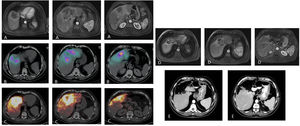

Paciente con carcinoma de recto estadio IV por metástasis única que afecta los segmentos centrales IVa, IVb y VIII tratada con quimioterapia neoadyuvante (FOLFOXIRI) con respuesta minor (A). Con la intención de reducir el tamaño tumoral (que requería cirugía hepática extrema) y como test del tiempo (primario no resecado y comportamiento tumoral incierto), se valora al paciente como candidato a RE. La SPECT/TC tras la inyección de MAA a través de las arterias segmentaria del VIII y accesoria de la hepática izquierda (B) muestra el adecuado acceso al tejido tumoral, con llegada a parte del tejido no tumoral pero con preservación de todos los segmentos hepáticos posteriores. Se administran 2,3 GBq de 90Y-microesferas de resina. El estudio dosimétrico en el PET de 90Y (C) calcula una dosis absorbida media en el tumor de 120 Gy y en el tejido no tumoral de 74,7 Gy. El estudio de resonancia magnética ocho meses después de la RE (D) muestra una reducción significativa del tamaño tumoral, lo que permite realizar una hepatectomía central laparoscópica (E) con mínima pérdida de sangre e ingreso de tres días. El paciente sigue vivo 72 meses después de la RE y ha permanecido libre de enfermedad tumoral hepática 54 meses tras la cirugía (presentó lesión metastásica en el segmento V/VIII que fue nuevamente resecada).